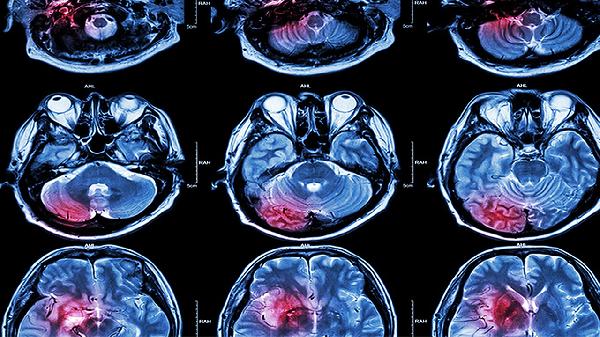

颅内静脉系统血栓形成通常由感染、脱水、血液高凝状态等因素引起,表现为头痛、视乳头水肿、癫痫发作等症状。脑动脉血栓形成多与动脉粥样硬化、房颤等疾病相关,常见症状包括偏瘫、失语、意识障碍等。影像学检查是鉴别两者的重要手段,CT静脉造影对颅内静脉系统血栓形成诊断价值较高,而CT血管造影或磁共振血管成像更适合诊断脑动脉血栓形成。